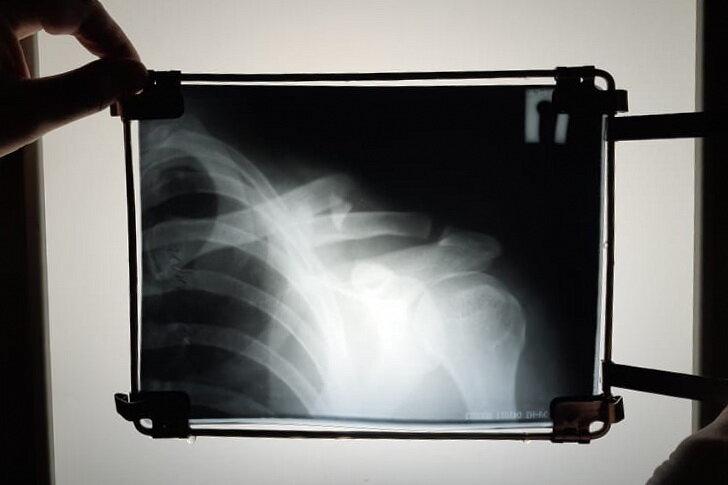

Довольно часто во время приема приходится слышать от пациентов что-то вроде - «Доктор, мне уже делали рентген, только я снимки дома (в машине, на работе) забыл(а)» или «Я от Вашего рентгена скоро светиться буду». Рентгенография с момента открытия в 1895 году и до сих пор является одним из самых распространенных методов исследования. Врачам-травматологам в современном мире без неё было бы непросто ставить правильные диагнозы и лечить пациентов с переломами костей. Несмотря на современное развитие высокотехнологичных методов лучевой диагностики (УЗИ, КТ, МРТ, ПЭТ-КТ), значение рентгенографии трудно переоценить. Рентгенологическое исследование применяется как при диагностике травм и заболеваний костно-мышечного аппарата, так и для контроля процесса выздоровления. Это объясняет необходимость повторных исследований в ходе обследования и лечения. Помимо этого случается, когда пациенты забывают или теряют свои «снимки», а на приеме у врача интерпретация рентгенограмм может имет

Рентгенография с момента открытия в 1895 году и до сих пор является одним из самых распространенных методов исследования. Врачам-травматологам в современном мире без неё было бы непросто ставить правильные диагнозы и лечить пациентов с переломами костей. Несмотря на современное развитие высокотехнологичных методов лучевой диагностики (УЗИ, КТ, МРТ, ПЭТ-КТ), значение рентгенографии трудно переоценить.

Рентгенологическое исследование применяется как при диагностике травм и заболеваний костно-мышечного аппарата, так и для контроля процесса выздоровления. Это объясняет необходимость повторных исследований в ходе обследования и лечения. Помимо этого случается, когда пациенты забывают или теряют свои «снимки», а на приеме у врача интерпретация рентгенограмм может иметь важное значение. В связи с этим приходится назначать повторные дополнительные исследования или переносить осмотр пациента на другой день, если больной отказывается от исследования. И вот тут возникает в голове пациента закономерный вопрос – «А не вредно ли это?».